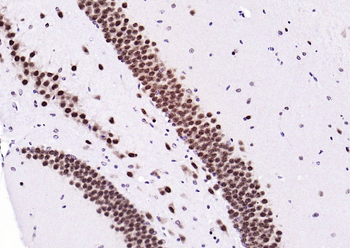

IHC staining of FFPE human brain with Ubiquitin antibody (clone PBQN-1). Required HIER: boil tissue sections in pH9 10mM Tris with 1mM EDTA for 10-20 min followed by cooling at RT for 20 min.